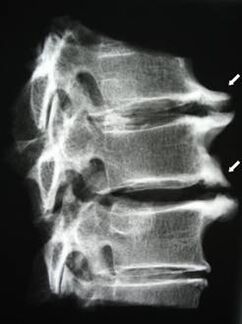

Στα αρχικά στάδια, η οστεοχόνδρωση ανιχνεύεται με μαγνητική τομογραφία. Αργότερα, η παθολογία μπορεί να διαγνωστεί χρησιμοποιώντας ακτινογραφία. Στις ακτινογραφίες της αυχενικής μοίρας της σπονδυλικής στήλης είναι αισθητή η μείωση της απόστασης μεταξύ των σπονδύλων, οι παθολογικές αλλαγές στις αρθρώσεις της όψης και η οστεοφυτία.